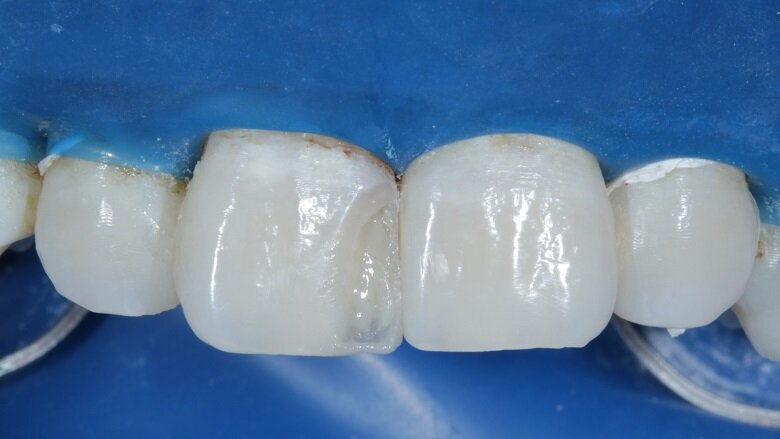

The shades that were selected were A2 Dentin, A2 Body and A2 Enamel. After this, isolation was achieved with a rubber dam (Fig 6). The caries of both 11 and 21 were excavated using a small round carbide bur (Fig 7). Primary and secondary bevels were given on tooth no 11 (Fig 8). After re-evaluation of the mesio-distal width of both the incisors, slight enameloplasty was done on tooth no 21 (Fig 9).

Total etch was done on both teeth with 37% phosphoric acid on the roughened surfaces for 30 seconds (Fig 10) and thoroughly washed with water. Bonding agent was applied and air dried for 20 seconds (Fig 11).

The tooth surface was then cured for 20 seconds. A free hand palatal shell was built using A2 enamel shade which gave the restoration a basic structure and is the first step of layering (Fig 12). Tooth no. 21 was built up palatally using A2 dentin and body shade.